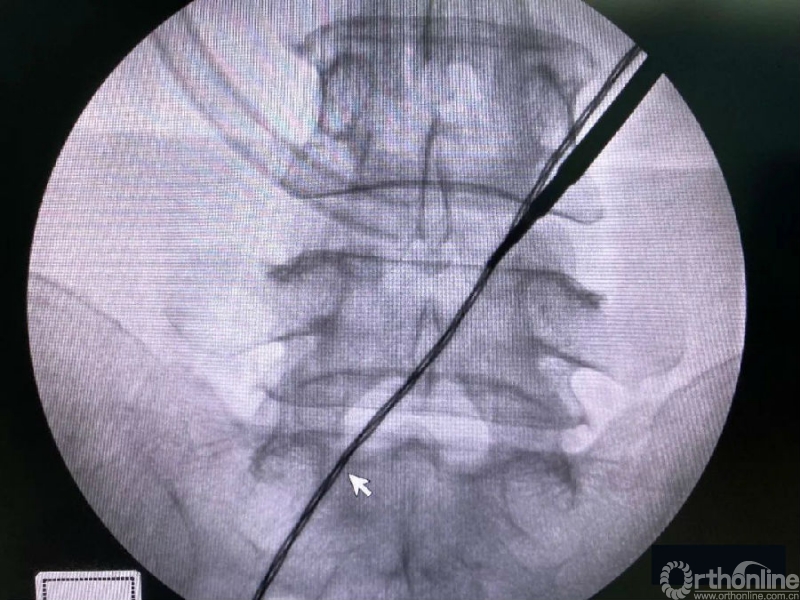

术中第一次及第二次的两个定位孔